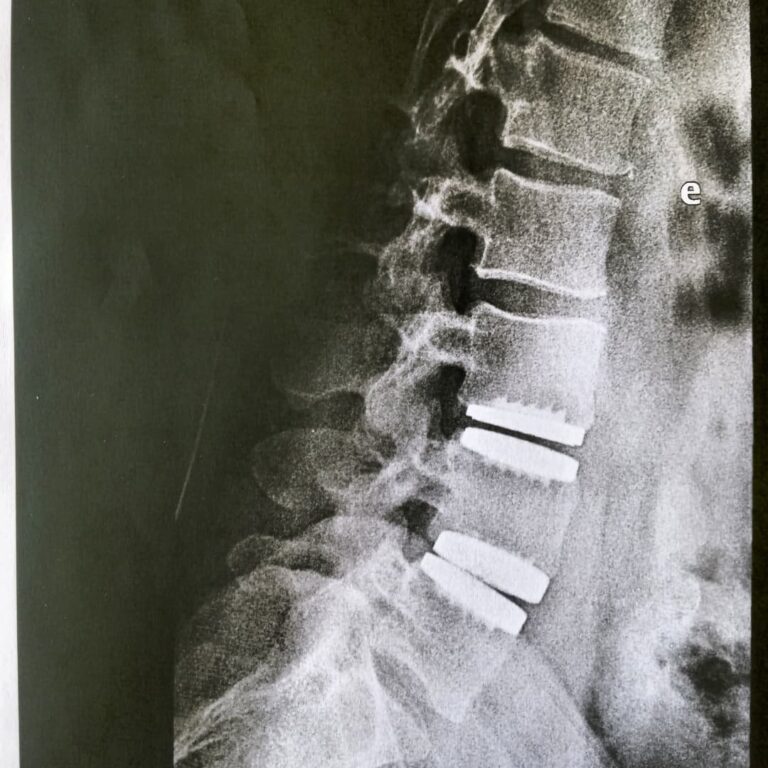

A cirurgia minimamente invasiva na coluna vertebral é um tipo de cirurgia que usa técnicas avançadas e instrumentação especializada para operar com mínima perturbação aos tecidos circundantes.

Pacientes com dores crônicas na coluna que não respondem a tratamentos conservadores, aqueles com discos herniados, estenose espinhal, fraturas vertebrais e algumas deformidades da coluna podem ser candidatos à cirurgia minimamente invasiva.